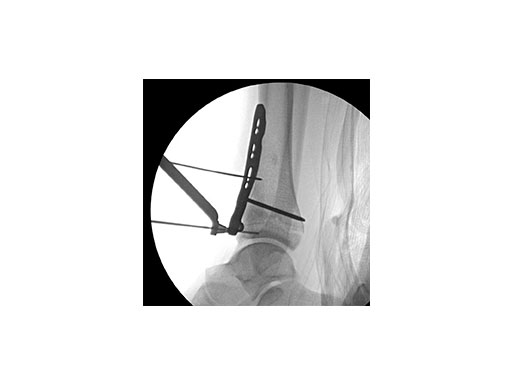

Surgeons performed an anterolateral surgical approach and distracted the joint using the distraction clamp and osteotome (Fig 2). The fracture was fixated with a VA-LCP Anterolateral Distal Tibia Plate (Fig 35).

Case 2: Scaffolding fall (Case provided by Mark Lee, Sacramento, USA)